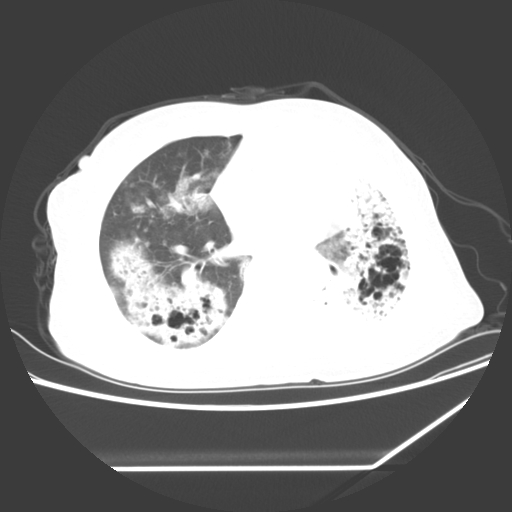

标题: CT25393:病人45岁,咳嗽,吐黄痰带血丝,发热,胸闷月余 [打印本页]

标题: CT25393:病人45岁,咳嗽,吐黄痰带血丝,发热,胸闷月余

1、左肺中央型肺癌并双肺弥漫性转移   2、双肺部感染    3、肺大泡     4、左侧胸腔积液

双侧肺弥漫性病变,可见“空泡征”及“蜂窝征”,考虑肺泡癌可能性大,左侧胸腔积液,考虑胸膜受累可能!

1)不排除肺泡癌可能。2)左侧胸腔积液。